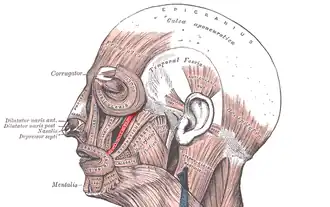

Muscles of the head, face, and neck. | |

Zygomaticus minor muscle (shown in red).

Zygomaticus minor muscle (shown in red).